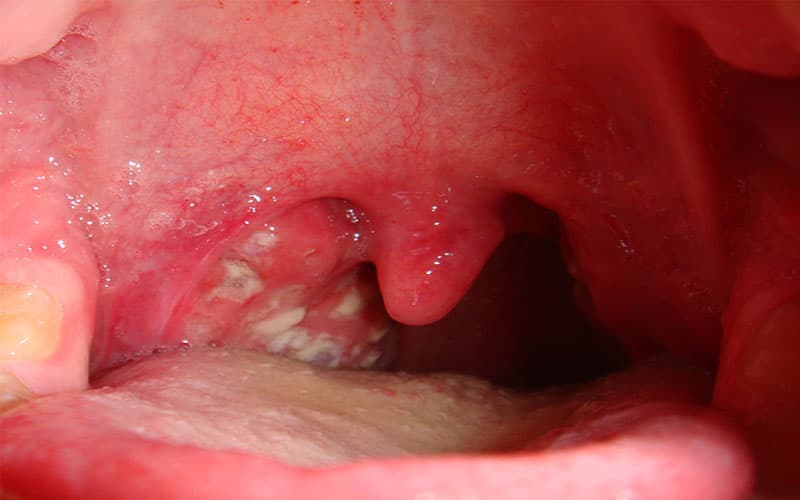

Một đặc điểm đặc trưng của thể bệnh này là sự hình thành màng giả màu xám trắng trên amiđan, sau đó lan ra các vùng như thanh quản, mũi, lưỡi gà, vòm họng, hầu. Màng giả bám chặt vào các mô bên dưới, và khi cố gắng tách ra có thể gây chảy máu. Qua quá trình thăm khám, phát hiện màng giả là đủ để chẩn đoán bệnh và cần điều trị bạch hầu ngay lập tức, không cần chờ kết quả xét nghiệm.